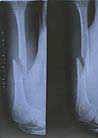

浙江省项进英被打至骨折

浙江省项进英

进京上访遭公安毒打,左胳膊肱骨骨折